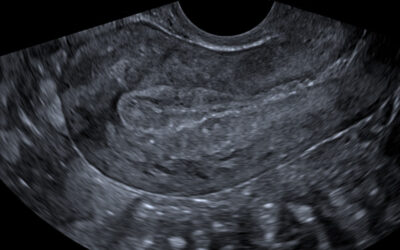

УЗД органів малого тазу (жіночих статевих органів)

Здоров’я жінки – це основа її щастя. УЗД жіночих статевих органів – це один із найважливіших методів профілактики гінекологічних захворювань. Регулярне проходження вагінального УЗД дозволяє виявити патології на ранніх стадіях і запобігти розвитку ускладнень. Чому УЗД...